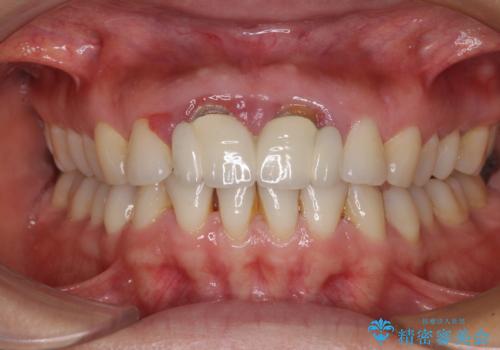

- 隙間の空いた前歯をセラミッククラウンで補隙したところ、歯肉から出血してしまい、何とかしたいとのことで来院された患者様です。

初めは前歯のみの処置で改善を希望されていたため、広範囲に処置範囲を広げることで歯の幅がバランスする治療を提案しましたが、削らなければならない歯が増えてしまうため、患者様と相談して全顎矯正により前歯のスペースを閉じていくこととしました。

不適合なクラウンが装着されていたため、歯周ポケットが深くなっていましたので、矯正治療前に歯周外科処置を行って歯周ポケットを除去し、矯正治療後にオールセラミッククラウンにて補綴治療を行うこととしました。